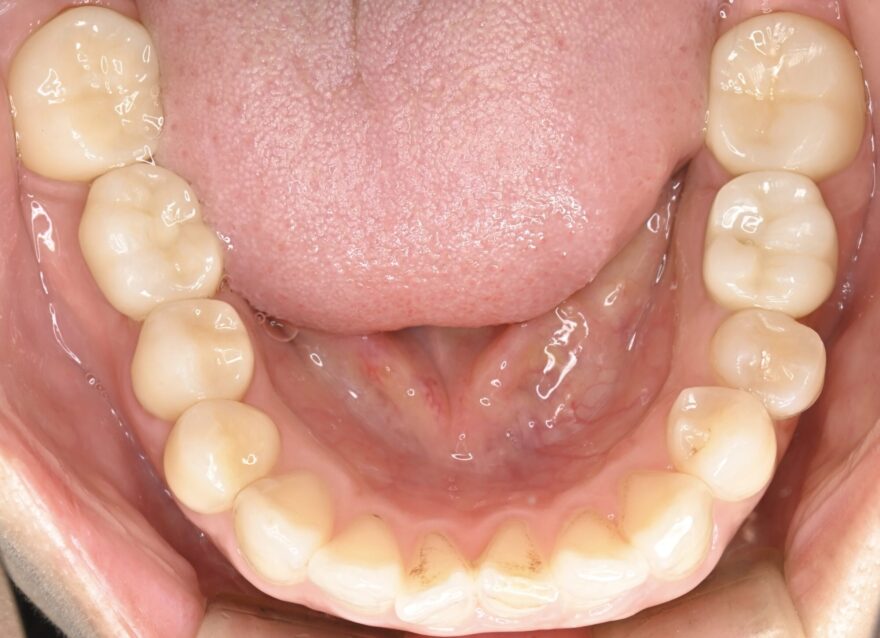

治療後の口腔内写真

左上の八重歯を抜くことで、よりバランスが取れた美しさになりました。